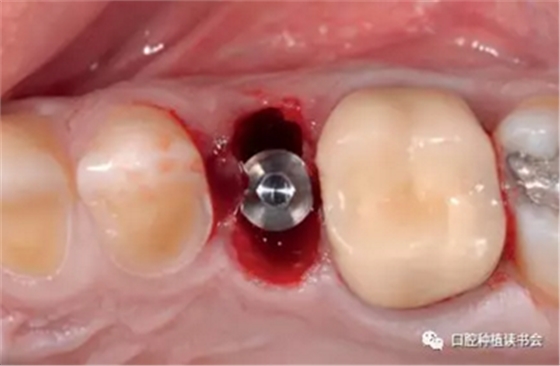

4.2.3 植入Nobel active種植系統(tǒng) RP 13mm種植體,植入扭矩大于45Ncm,初期穩(wěn)定性良好(圖11、圖12))。

圖11 使用Nobel active手用植入扳手精確控制植入方向

圖12 種植體初期穩(wěn)定性良好,注意與唇側(cè)骨板間的間隙